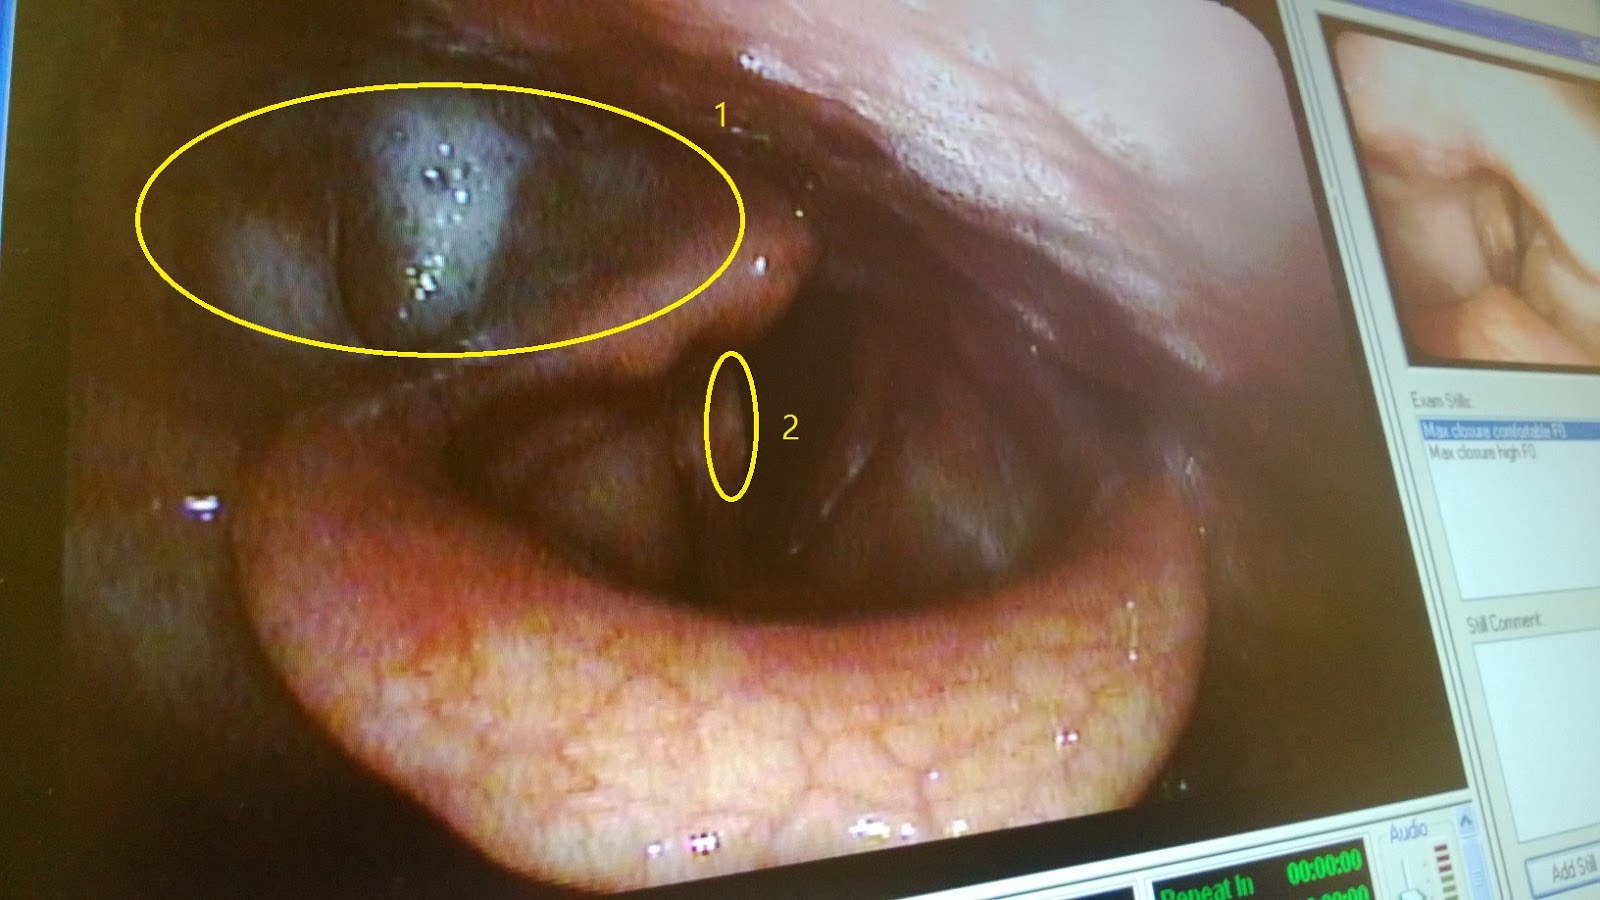

Jan has me start by making an E sound for as long as I can, hum the birthday song, a couple different phrases, a higher pitch E sound for as long as I can hold it.  Which was about 8 seconds, not very long…  All the while they’re looking at the monitor to see what my vocal folds and other areas around them are doing while I’m making these sounds.  They eventually pull the scope out and we start talking about what they were seeing.  He mentions that the right vocal fold is shot, which we all knew already.  He also mentions about something being flaccid in there., I wish I could remember what it was called!  I asked if that was a good or bad thing.  He said it’s not a good thing.  Essentially, because the muscle on the right side of my throat isn’t doing anything it’s kind of pulling away from the throat which causes what he called a “lagoon” for things to fall into.  You’ll see this in a picture that I’ll post at the end.  He then tells me that he’s really glad I didn’t get the implant done today as there’s still material from the injection I had several months ago in the vocal fold.  If I had the implant surgery today, the size of the implant would’ve been used based on the way my vocal folds are now.  Eventually, that material would dissolve like the rest of it has and I’d likely be back to where I am now to an certain extent.  We talk some more about the findings, then he leaves with Jan and the lady from Turkey and the Wet Hand lady.  The nurse then shows me the video from the scope and talks me through what they were seeing and points out the “lagoon” and the material in the vocal fold.  I’m absolutely fascinated by this.  She eventually leaves the room and I grab a picture of the monitor, the one you’ll see later.

1. This is the “lagoon” that he spoke of. Notice it isn’t like that on the opposite side.

2. This is the Right Vocal Cord.  The yellowish color is the remaining material from the previous injections.  Over time this will dissolve.